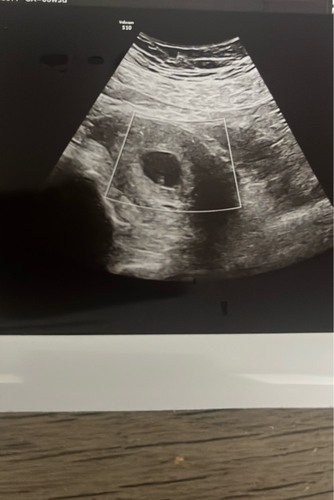

Ik ben zelf gisteren met 7+4 geweest en hetzelfde bericht gekregen. Mijn wereld stortte in. Het was te klein voor mijn termijn en er was geen kloppend hartje. Ik weet het exact doordat mijn eisprong dmv fertiliteitstraject is gemonitord. Bij mag zag het er als volgt uit. Ze heeft niets over een termijn gezegd, maar als ik ze vergelijk lijken onze foto’s redelijk op elkaar. Ik moet as woensdag weer terug. Ze was bij ons redelijk duidelijk en gaf geen hoop op verbetering.